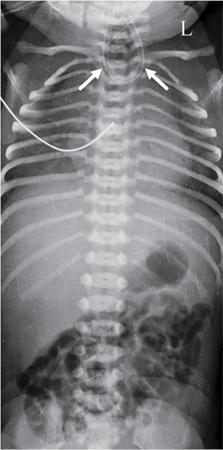

C.V. Kanimozhi, S. Muralinath, Raveendran J. Many of the important congenital gastrointestinal abnormalities present acutely in the newborn; some present much later. These include obstructive gastrointestinal lesions that present with vomiting, abdominal distension and not having passed meconium. The imaging modalities that are most commonly used in the evaluation of neonatal gastrointestinal abnormalities are plain films, contrast studies and ultrasound. Plain films remain a valuable tool in the assessment of abdominal abnormalities in the neonate. They are also an excellent guide to determining the next proper imaging study to perform for a particular problem. Certain neonatal bowel disorders have a pathognomonic appearance on radiographs obviating the need for further imaging. The essential and basic view to be done at the bedside is the supine view of the abdomen. In the evaluation of abnormal intra-abdominal gas patterns, alternative decubitus views, prone and supine cross-table lateral views may be taken. Erect view is not utilized in neonatal practice at the bedside as it is impossible to restrain a neonate in that position and unnecessarily subjects the neonate to stress, which may worsen the condition of an already sick baby. Evaluation of the bowel gas pattern and the anatomic localization of the intra-abdominal gas is the key to diagnosis in the evaluation of diseases of the GI tract. The bowel gas in the neonate is essentially swallowed air (Box 7.8.1). Movement of Air Through the GIT in a Term Neonate Most infants pass meconium by 24 hours of life. In order to interpret the bowel gas pattern and determine if an abnormality is present, it is crucial to know the age of the neonate (hours since birth) at the time the radiograph was taken. When there is impaired swallowing, such as due to CNS depression or in prematurity, radiographs show diminished bowel gas. In cases of bowel atresia, radiographs show absence of bowel gas in distal segments. Thus, the distribution of bowel gas and its pattern serve as pointers to the diagnosis. After the radiograph has been done, depending on the findings, an ultrasound or fluoroscopic contrast study may be performed next. The radiologist should tailor the contrast study to suit the particular patient and the clinical question that needs to be answered. In cases of suspected high GI obstruction, an upper GI contrast series is study of choice; in cases of suspected low GI obstruction a contrast enema should be performed to delineate the anatomy. When performing fluoroscopic studies, it is important to bear in mind the radiation dose and to adopt the ALARA principle. Minimizing radiation exposure in children is important because they are more sensitive to the effects of radiation and have a longer life expectancy than adults. The technical parameters must be adapted to paediatric imaging. Ultrasound is a useful bedside tool particularly in the sick neonate. In neonates, the sonographic image resolution is excellent due to the lack of significant body fat. In neonates, exquisite images of the abdomen can be obtained with the high-resolution ultrasound probe, which permits imaging the bowel wall in great detail. In addition, it can also reveal other causes for abdominal distension or vomiting. In this chapter, we will discuss the aetiology, clinical presentation and imaging appearances of congenital neonatal gastrointestinal abnormalities. We will also discuss common acquired abnormalities that present in the neonatal period, namely necrotizing enterocolitis. Congenital oesophageal malformations of the newborn include the various types of atresia (with and without fistula) and oesophageal duplications. Oesophageal atresia with or without tracheoesophageal fistula (TEF) is a common congenital anomaly that manifests in the neonatal period. It is also the most important congenital malformation of the oesophagus. Oesophageal atresia is commonly associated with other anomalies of the gastrointestinal tract such as imperforate anus, pyloric atresia, duodenal atresia and annular pancreas and less frequently with anomalies of the cardiac and genitourinary systems. About 20% of patients with oesophageal atresia have the VACTERL syndrome (vertebral anomaly, anorectal atresia, cardiac lesion, tracheoesophageal fistula, renal anomaly, limb defect). Oesophageal stenosis and webs may be associated with oesophageal atresia. The aetiology of oesophageal atresia and TEF is not completely understood. Faulty separation of the primitive trachea and oesophagus is the most widely accepted theory. The way the primitive foregut cleaves into a ventral (tracheal) passage and a dorsal (oesophageal) passage is a complex process and is poorly understood. Folds developing from the longitudinal ridge is said to separate the two. When the separation has an extreme tracheal bias, an oesophageal atresia occurs and if the bias is towards the oesophagus, then a tracheal atresia ensues. Incomplete separation may result in fistula of various types. Oesophageal atresia and TEF are classified depending upon the absence or presence and location of the fistula between the oesophagus and the trachea (Fig. 7.8.1). Neonates present within a few hours of birth with excessive salivation, drooling, cyanotic spells and regurgitation of feeds. The inability to successfully pass a nasogastric tube strongly suggests oesophageal atresia. Newborns with H-type fistula may have feeding difficulties and choking, but often the presentation and diagnosis is only later in infancy when the patient presents with cough, choking episodes and recurrent pneumonia. The role of imaging is to diagnose, define the anatomy to the best extent possible and evaluate for other anomalies to provide a clear picture for the paediatric surgeon. For example, it is important for the surgeon to know the side of the aortic arch in order to lateralize the surgical approach. Chest X-ray and Echo can localize the arch and determine if an anomalous right-sided aortic arch is present. Plain films of the chest including abdomen need to be obtained. The radiograph will demonstrate the air-filled distended proximal oesophageal pouch. If a nasogastric tube has been inserted, the coiled tube will be seen within the pouch. Absence of bowel gas in the abdomen indicates oesophageal atresia without a distal fistula – types A and B have this radiographic appearance (Fig. 7.8.2). The presence of gas in the gastrointestinal tract indicates the presence of a distal fistula – types C and D (Fig. 7.8.3). Contrast studies to delineate the proximal pouch are generally not indicated. Coiling of the nasogastric tube in the proximal pouch confirms the diagnosis. Chest radiographs frequently show changes of consolidation due to aspiration pneumonia, most often involving the right upper lobe (Fig. 7.8.4). In cases of H-type fistula, plain films are nonspecific and the diagnosis depends on contrast studies. Radiological diagnosis is made by means of a tube oesophagogram. This study has the potential risk of aspiration and the neonate may desaturate quite rapidly. Hence, it is important to have neonatal emergency resuscitation at hand. The tube oesophagogram is performed under fluoroscopy with the baby in lateral- or steep-prone oblique position. The NG tube is placed at the oesophagogastric junction and is gradually withdrawn while simultaneously injecting contrast. Nonionic low-osmolar contrast agent should be used. Most of the H-type fistulas are located in the lower cervical and upper thoracic regions with the fistula typically coursing upward and forward from the oesophagus. In the presence of a fistula, the contrast will be seen passing into the trachea in an upwardly oblique configuration. Aspiration during the study can also cause the contrast to appear in the tracheal tree and the lungs. It needs to be established whether the contrast has passed through the fistula or whether aspiration has occurred. Recording of the fluoroscopic run and reviewing the images may be required to make this distinction. Repeat examination may be required. Demonstration of H-type fistula can be difficult radiologically. In such patients, bronchoscopy with transfistula guidewire placement has been found to be of use. MRI – High resolution structural MRI is a new technique that is being used to visualize tracheobronchial anatomy. The disadvantage with radiographs is that one cannot determine the anatomic subtype of TEF, the site of the TEF or the length of the gap between the atretic segments. Using ultrashort echotime (UTE) MR imaging, it is possible to visualize the exact site of the fistula and assess the size of the oesophageal gap. This can aid presurgical planning and help identify infants at risk for complications, such as those with a long oesophageal gap. Imaging plays an important role in the evaluation of early and late complications of atresia repair. Early complications include anastomotic leaks and are seen in about 10%–20% of cases. Oesophageal contrast study, using a nonionic low-osmolar contrast agent, is performed to demonstrate the leak at the anastomotic site (Fig. 7.8.5). Leaks are associated with a greater incidence of subsequent stricture development. Anastomotic stricture is a common complication seen in about 30%–40% of cases. Often there is a slight narrowing at the site of repair without the patient having any difficulty in swallowing (Fig. 7.8.6). The anastomotic narrowing is clinically relevant only if the patient has dysphagia; such cases respond to dilatations. Recurrent TEF occurs in 5%–10% of cases after oesophageal atresia repair. Late complications include dysphagia, gastroesophageal reflux, tracheomalacia and chest wall deformities. Dysphagia can occur post-operatively due to abnormal oesophageal motility. Oesophageal dysmotility can be caused by abnormal neural development of the oesophagus or may result from complication of atresia repair. Gastroesophageal reflux affects 40%–65% of patients following oesophageal repair. It may be due to an intrinsic deficiency in the motor function of the oesophagus; this may get exacerbated postrepair due to an alteration of the anatomical gastroesophageal junction. Oesophageal atresia key imaging finding – X-ray shows NG tube coiled in proximal oesophageal pouch. The stomach is divided into the fundus and body proximally and the antrum distally. The antrum is divided by the sulcus intermedius into a proximal pyloric vestibule and a distal pyloric antrum or pyloric canal. This canal terminates into the pyloric sphincter beyond which is the duodenum. Congenital anomalies of the stomach that manifest in the neonatal period are uncommon. Hypertrophic pyloric stenosis (HPS) is the most common surgical cause of vomiting in infants. The incidence is 2–5 per 1000 live births, with geographic and racial variations. Compared to Caucasians, HPS is less common amongst Asian populations. The male to female ratio is approximately 4:1, occurring more commonly in the first-born child. The precise aetiology is unknown. Overactivity or prolonged spasm of the circular muscle of the pyloric antrum is thought to be the primary problem in these infants. This spasm leads to muscle hypertrophy and obstruction. Multiple hypotheses have been proposed for this prolonged spasm. One is that some infants are genetically predisposed to increased gastrin production which leads to a vicious cycle of hyperacidity, increased gastric contraction and secondary development of muscular hypertrophy. Most infants present after the first week of life and before 3–4 months of age. Typical symptoms include projectile nonbilious vomiting, regurgitation and difficulty in feeding. The gastric outlet obstruction can lead to emaciation. The distended stomach with active peristaltic activity may be visible through the thin abdominal wall. In the past barium upper GI series was the mainstay diagnostic tool for HPS. Prior to the barium study, the stomach may need to be decompressed via a nasogastric tube. The classic sign on a barium study is the ‘string sign’ (Fig. 7.8.7) produced by a thin stream of barium in an elongated narrowed pyloric canal; the canal typically curves upward. In severe cases, complete obstruction will lead to the ‘beak sign’, which is produced by beaking of the contrast as it enters the pyloric canal. With lesser degrees of obstruction, the ‘double track sign’ is seen. This is produced when the pyloric canal is flattened and the barium accumulates in the crevices along either side of the flattened canal. Pylorospasm can transiently mimic the findings of HPS. Currently, ultrasound is the modality of choice for the diagnosis of HPS and upper GI studies are seldom used. Ultrasound is considered the ‘gold standard’ as it allows direct examination of the pyloric muscle and also provides the ability to perform a dynamic study. The ultrasound examination is performed with a linear high-frequency transducer (6–10 MHz). The examination begins with the baby in supine position. First, the antropyloric region is identified; the pylorus is usually located medial and posterior to the gall bladder. The normal pyloric muscle is a thin hypoechoic layer that measures 2 mm or less. The abnormal pyloric canal shows thickening of the muscle and the mucosa to varying degrees. In cross section, it is seen as a hypoechoic structure likened to a doughnut. The length of the canal is measured in long section where its appearance is likened to the cervix. The sonographic diagnostic criteria for HPS are a thickened muscle layer measuring ≥3 mm and an elongated pyloric channel ≥15 mm (Fig. 7.8.8). The diameter of the pylorus in cross section was also one of the originally used measurements. However, due to a significant overlap between normal and abnormal, this measurement is no longer utilized. Additional ultrasound findings of HPS are hypertrophy of the pyloric mucosa and a distended, actively peristalsing stomach. The hypertrophied redundant mucosa projects into the antrum analogous to the ‘nipple sign’ in barium studies (Fig. 7.8.8D.). Colour Doppler imaging shows increased flow in the muscle and mucosa. The above-described measurements of pyloric muscle thickness and canal length are vital to diagnosis. However, dynamic assessment is equally important. One must evaluate the antropyloric region over a period of time to ensure persistent stenosis without evidence of relaxation and opening of the canal. A distensible antropyloric region with normal passage of gastric contents excludes HPS. Transient contractions of the pylorus or pylorospasm can mimic pyloric stenosis in both measurement and appearance. With observation over a period of time, opening of the pyloric canal may be visualized. Hence the key to diagnosis of HPS is persistent non-relaxing thickened musculature. Gas in the stomach may obscure the pylorus. To avoid this, place the infant in an oblique position, right side down which will allow the antrum to fill with fluid. Conversely, an overdistended fluid-filled stomach can displace the pylorus dorsally. In such cases, turning the infant left side down will displace the fluid towards the fundus and will allow the pylorus to rise to a more anterior position. At times, equivocal examinations may occur where the muscle measures 2–3 mm in thickness and does not relax. In these patients, careful monitoring with repeat ultrasound is warranted. In a few cases, the abnormalities advance overtime to fully developed HPS. Hence in such equivocal cases if vomiting continues, follow-up ultrasound is advisable. Surgical pyloromyotomy is the treatment for HPS. On ultrasound, the myotomy site can be seen as an interruption in the hypoechoic doughnut. It is important to be aware that postsurgery, the pyloric muscle may remain thickened for up to 5 months with a gradual return to normal thickness. In the first week after surgery, the muscle can be the same thickness as pre-op or even thicker. One should not be alarmed by this appearance. The dimensions gradually return to normal over the course of a few months. Postop if the child is thriving well, there is no need for imaging to be performed. HPS key imaging finding: On high-frequency ultrasound muscle thickness ≥3 mm and elongated pyloric channel ≥15 mm. Pyloric atresia is a rare anomaly comprising less than 1% of all intestinal atresias. Pyloric atresia is classified into three types (Fig. 7.8.9): The exact aetiology remains controversial. In the past, it was postulated that failure of recanalization of the gastrointestinal tract was the cause. Recent evidence suggests that pyloric atresia is the result of localized vascular occlusion. This vascular theory suggests that the atresia is due to focal ischemia secondary to intrauterine stress, vascular insult or anoxia. In complete obstruction, the presentation is in the neonatal period with nonbilious vomiting within the first few hours of life. Incomplete obstruction due to a diaphragm has a variable presentation depending on the size of the orifice. These patients can present later in life with intermittent vomiting or postprandial vomiting. In complete pyloric atresia, a dilated stomach is present on radiographs with absence of gas in the distal bowel. This is known as ‘single bubble’ appearance (Fig. 7.8.10). This appearance is diagnostic and in such cases, contrast studies are generally not required. In the membranous type, there is an opening in the centre of the diaphragm and hence, the obstruction is usually incomplete. On radiographs, the stomach is distended and lesser than normal volumes of air is present in the small bowel (Fig. 7.8.11). On upper GI barium studies, a diaphragm is seen as a thin (2–4 mm) linear filling defect that spans across the antrum with a normal pyloric canal. One needs to determine on fluoroscopy whether the membrane is causing significant obstruction or not. If obstructing, the diaphragm will balloon out with gastric peristalsis. In incompletely obstructing diaphragms, the edges of the diaphragm will be visible but there will no obstruction or ballooning. Pyloric atresia key imaging finding: X-ray abdomen – ‘single bubble’ appearance. Microgastria is an extremely rare congenital abnormality wherein the stomach is small, midline in position and typically associated with a dilated oesophagus. The stomach is represented by a small tubular structure without recognizable differentiation into fundus, body, antrum and pylorus. Agastria is the most extreme form of microgastria. Microgastria is frequently associated with other anomalies such as polysplenia-asplenia syndrome, malrotation, gastrointestinal atresia and vertebral, cardiac, renal and limb reduction anomalies (VACTREL association). Microgastria occurs due to arrest in early development of the foregut. In the 5th week of gestation, dilatation of the region of the future stomach occurs. Ninety-degree rotation of the stomach occurs in the 6th week, followed by development of the greater and lesser curves and growth of the fundus in the subsequent weeks. Arrest of this process leads to microgastria, with severity dependent on the stage at which arrest occurs. The development of spleen within the dorsal mesogastrium of stomach explains the association of microgastria and splenic anomalies. The association of limb, cardiac, tracheoesophageal, vertebral and renal anomalies has been attributed to impairment of early mesodermal development. The symptoms are related to the effects of the inadequate stomach and dilated oesophagus or due to the associated severe anomalies. These babies may present with feeding difficulties, failure to thrive, vomiting, recurrent aspiration and malnutrition due to severe gastroesophageal reflux. Radiographs may show an absent stomach bubble; in some cases, the shadow of the dilated oesophagus may be seen in the lower chest. On an upper GI study, the stomach appears small, tubular and midline in position. There is often associated severe gastroesophageal reflux and a very dilated oesophagus. The oesophagus dilates to take over the storage function of the inadequate stomach. Additional imaging studies are required to identify the associated anomalies. Key imaging finding: Upper GI study – Small, tubular stomach located in the midline. Congenital anomalies of the duodenum present with obstructive symptoms. The primary considerations for bilious vomiting in the neonate are duodenal atresia, duodenal stenosis, annular pancreas and malrotation with midgut volvulus. The most important investigation in the majority of these patients is an upper GI series as it accurately demonstrates the level and nature of duodenal obstruction. Duodenal atresia may be seen in isolation or in the setting of trisomy 21 (about 30% of patients have Down’s syndrome). Associated anomalies are frequent and include malrotation, oesophageal atresia, annular pancreas, biliary atresia, congenital heart disease and vertebral anomalies. Duodenal atresia is due to failure of gut recanalization during embryologic development leading to complete obstruction. Normal recanalization of the duodenum occurs between the 9th and 12th weeks of gestation. Failure of this process results in duodenal atresia. In most cases (roughly 80%), the atresia is distal to the ampulla of Vater. Neonates with duodenal atresia present with bilious vomiting in the first few hours of life. In those patients where the atresia is proximal to the ampulla, the vomitus will be nonbilious. In duodenal atresia, air is present in the stomach and duodenum with no gas in the distal intestinal tract. Dilatation of the stomach and the duodenum produces the characteristic ‘double bubble’ appearance on radiographs (Fig. 7.8.12). This appearance is diagnostic and rarely requires further imaging. Key imaging finding: X-ray abdomen – ‘double bubble’ appearance Duodenal stenosis and duodenal web cause partial obstruction due to a narrowed segment or thin membrane, respectively. As with duodenal atresia, both these conditions show a strong association with malrotation, annular pancreas and a preduodenal portal vein. Duodenal web and stenosis is due to incomplete recanalization of typically the second part of the duodenum. In babies with duodenal stenosis, the presentation and clinical findings depend on the degree of stenosis. Those with less severe forms of stenosis may present later in life. Radiographs in duodenal stenosis and web show a distended stomach and duodenum. Since the obstruction is incomplete, gas will be present in the distal loops. On upper GI study, duodenal stenosis is seen as a focal narrowing in the second part of the duodenum (Fig. 7.8.13). In duodenal web, a thin membrane/diaphragm is seen that partially obstructs the lumen, usually in the second segment of duodenum. The membrane is often difficult to demonstrate (Fig. 7.8.14). A ‘windsock deformity’ may also be seen; this appears as a proximal dilated duodenal segment with contrast outlining a thin web that bulges into a distal nondilated segment. This windsock duodenum is seldom seen in the neonatal period as this appearance is due to stretching of the membrane over time. Key imaging finding: Upper GI study – narrowing in second part of duodenum. Annular pancreas is an anomalous band of pancreatic tissue that encircles the second portion of duodenum. Annular pancreas may result in extrinsic duodenal obstruction. Often there is associated intrinsic duodenal abnormality viz. some degree of duodenal atresia, web or stenosis. As in duodenal atresia, associated anomalies such as trisomy 21, cardiac defects, malrotation, oesophageal atresia and anal atresia can occur. The pancreas arises as two endodermal outgrowths, ventral and dorsal buds, from the duodenum. The head of the pancreas derives from the smaller ventral bud. Annular pancreas occurs if the ventral bud becomes tethered to the duodenum or it fails to rotate completely before fusion with the dorsal bud. The clinical presentation is similar to duodenal atresia or stenosis. If the obstruction is complete, presentation is in the neonatal period with bilious vomiting. Cases of incomplete obstruction may remain asymptomatic until adulthood. Annular pancreas is the second most common condition to produce a ‘double bubble’ appearance on radiographs. Plain films will show dilatation of the stomach and duodenum. Upper GI contrast study will show narrowing of the second part of duodenum (Fig. 7.8.15). On ultrasound pancreatic tissue may be seen encircling the second part of duodenum (Fig. 7.8.16). At times the appearance may resemble a mass at the level of head of pancreas.